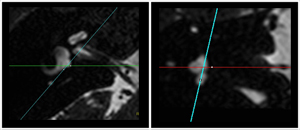

MRI imaging of the inner ear